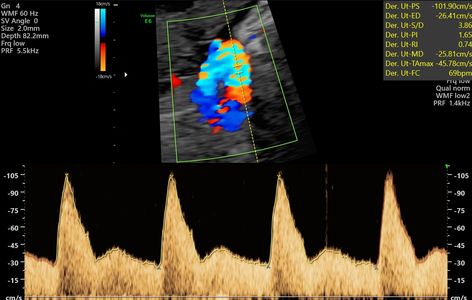

Eco que evalua el flujo de sangre por los vasos sanguíneos maternos y fetales. Su principal uso es en caso de que se sospeche problemas en el crecimiento de bebé.